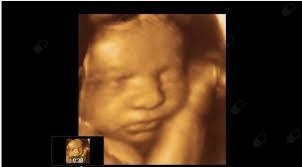

Foto e video